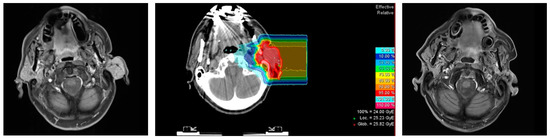

2.2. Treatment Characteristics

4.2. Radiotherapy

| Carbon Ion Radiotherapy | metric |

| Median GTV in cm3 (range) * | 37 (15–182) |

| Median CTV1 in cm3 (range) | 106 (32–594) |

| Median prescribed single dose in Gy RBE-weighted dose (range) | 3 (3–3) |

| Median prescribed total dose in Gy RBE-weighted dose (range) | 24 (18–24) |

| Number of beams (n) | |

| 1 | 7 |

| 2 | 8 |